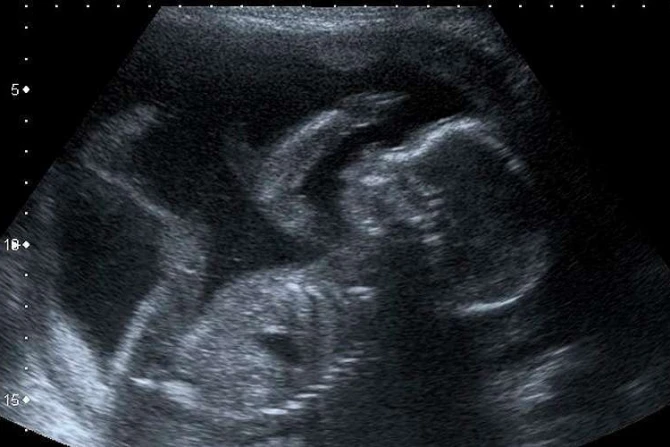

En declaraciones a ACI Prensa la Dra. Graciela Moya, que es pediatra, genetista y trabaja con médicos ecografistas, explicó que la “ecografía es un método que hace muchos años se utiliza de rutina en la clínica, sobre todo a nivel prenatal, porque es una herramienta que da muchísima información respecto de la anatomía fetal, de su ubicación, crecimiento y situación de salud”, y también “da información respecto a la mamá: de qué complicaciones podría tener”.

“Da una imagen que produce que las mamás, en general, se emocionen al ver al bebé”, aseguró.

“La ecografía lo que visibiliza es que eso que se está desarrollando en el vientre materno no es un conjunto de células, sino un ser humano que se desarrolla. Por lo tanto, lo que el médico le permite a la mujer embarazada es empezar a conocer a su propio hijo antes de su nacimiento”, resaltó.

“No nos olvidemos que en las manifestaciones provida se suele ofrecer ecografía en pantallas gigantes para que los asistentes confirmen que lo que una mujer lleva en su vientre no es un saco de células, sino un hijo gestándose”, acotó el politólogo.